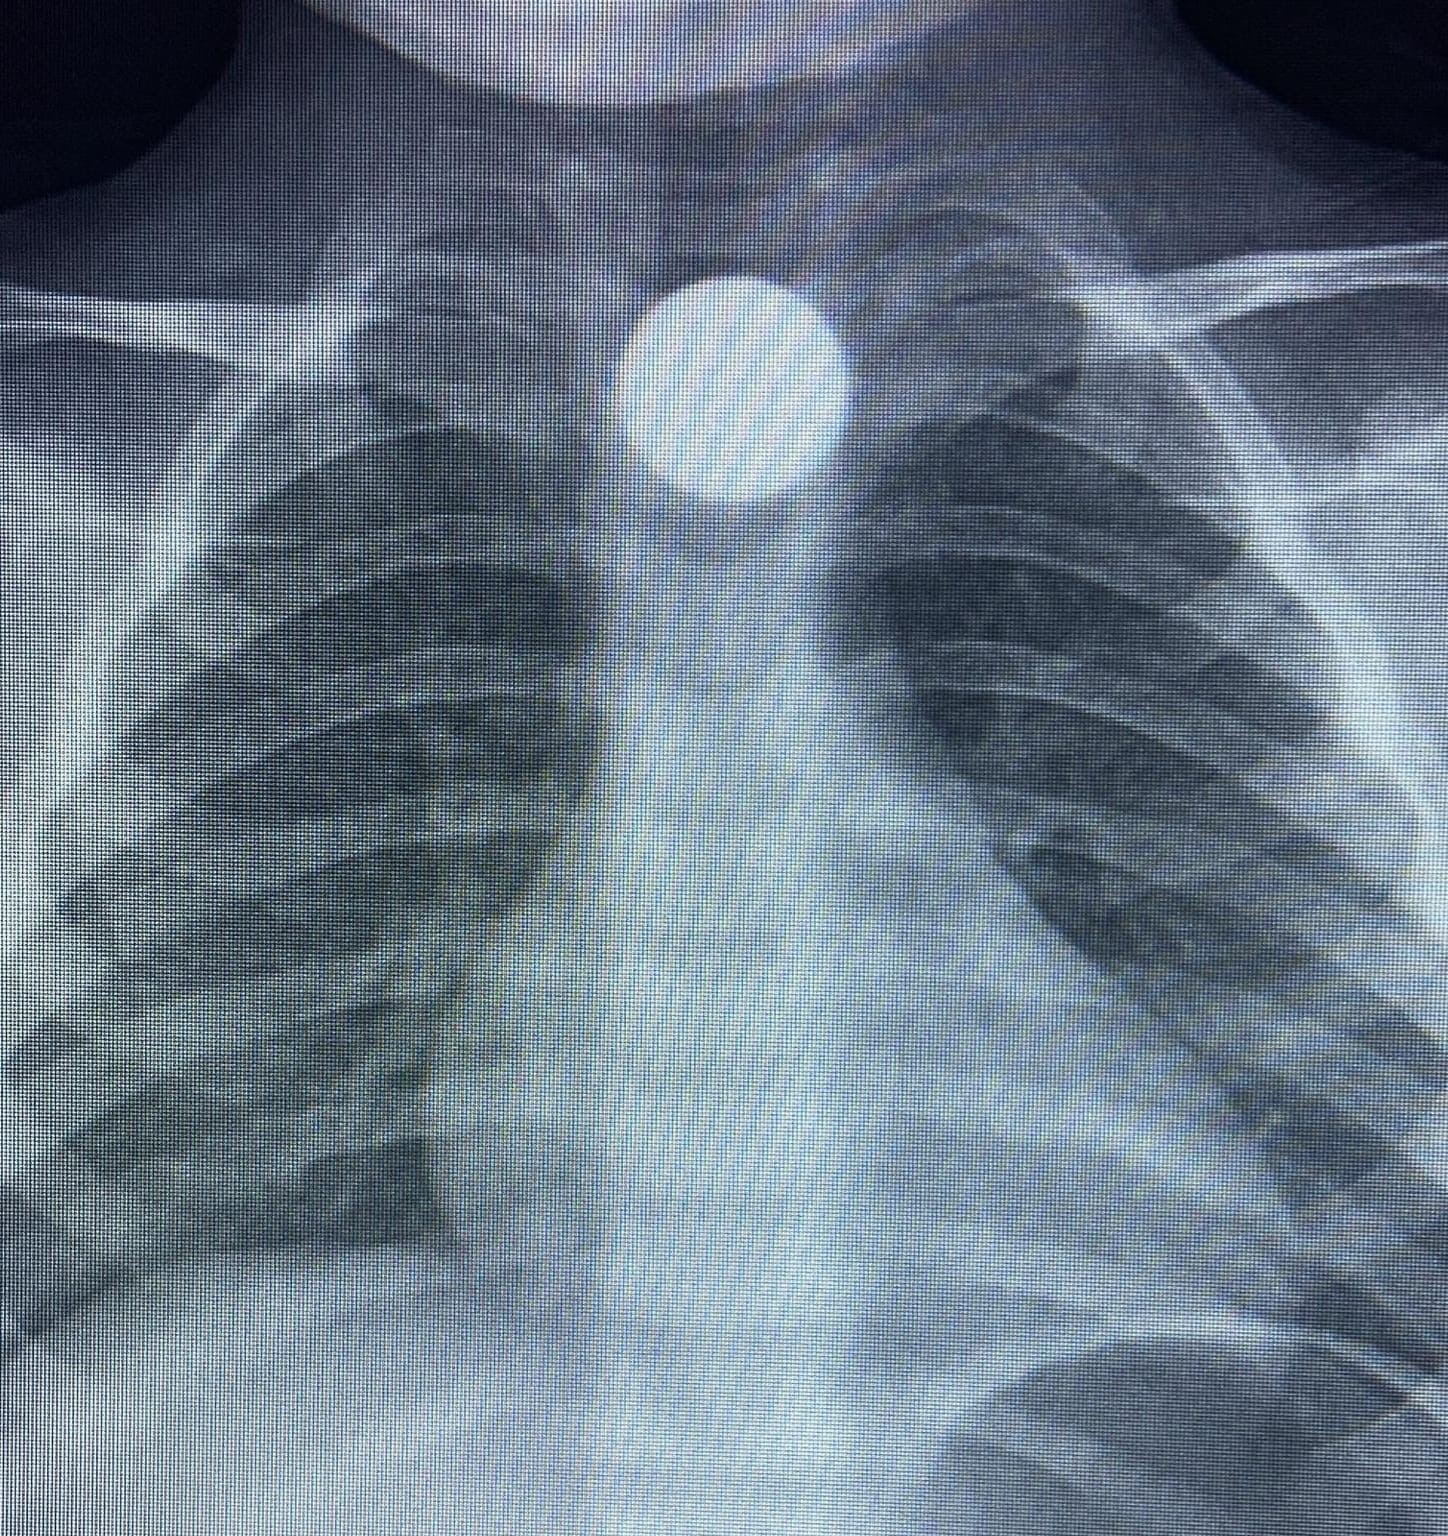

Olay, İnegöl'ün kırsal Yeniceköy Mahallesi'ndeki bir evde meydana geldi. 3 yaşındaki Bilal K., evde yerde bulduğu 50 kuruş madeni parayı ağzına atıp yuttu.

Olayı fark eden ailesi tarafından çocuk özel araçla İnegöl Devlet Hastanesi'ne kaldırıldı. Yapılan tetkiklerde yemek borusunda takılı kalan madeni para görüldü. Çocuk ilk tedavinin ardından ambulansla Bursa Yüksek İhtisas Eğitim Ve Araştırma Hastanesi'ne sevk edildi.